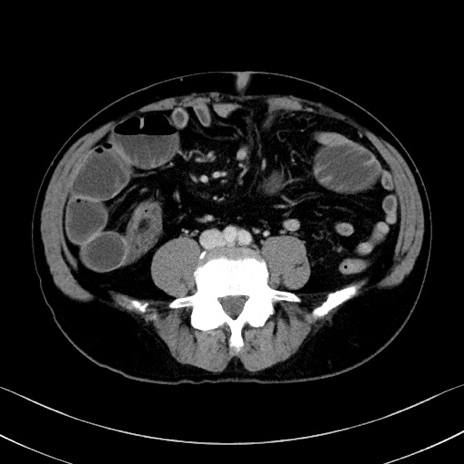

症例35(横断像)

【症例】70歳代 男性

【主訴】腹部膨満、嘔吐

【現病歴】昨日より腹部膨満感出現。本日増悪し、仙痛出現。嘔吐あり、受診。

【既往歴】糖尿病、胆摘後

【身体所見】BP 149/80mmHg、HR 74/min、BT 35.9℃、腹部:膨満、軟、圧痛なし。腸雑音減弱あり。上腹部正中切開瘢痕あり。

【データ】WBC 13500、CRP 1.72

冠状断像